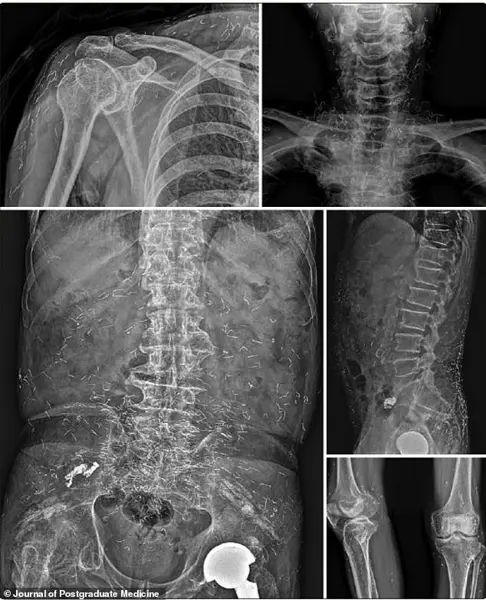

Doctors explained that the non-absorbable threads, implanted a decade earlier during acupuncture, had permanently settled in her leg tissue, acting as a persistent source of recurrent infection. 'These threads are inert and don’t break down,' noted a specialist at the time. 'But their presence can cause long-term damage, especially if they migrate to other parts of the body.' In 2022, a 73-year-old Korean man was hospitalized for a stroke.

During his evaluation, he described a 30-year history of widespread joint pain he had self-treated with gold thread acupuncture.

X-rays revealed thousands of the embedded threads throughout his body. 'This man had been using gold thread acupuncture for decades without any medical supervision,' said a neurologist involved in his care. 'His symptoms were so severe that he had to be hospitalized, and it was only through imaging that we realized the true extent of the problem.' Once a granuloma forms, treatment is challenging and often incomplete, as completely removing numerous, deeply embedded threads is difficult.